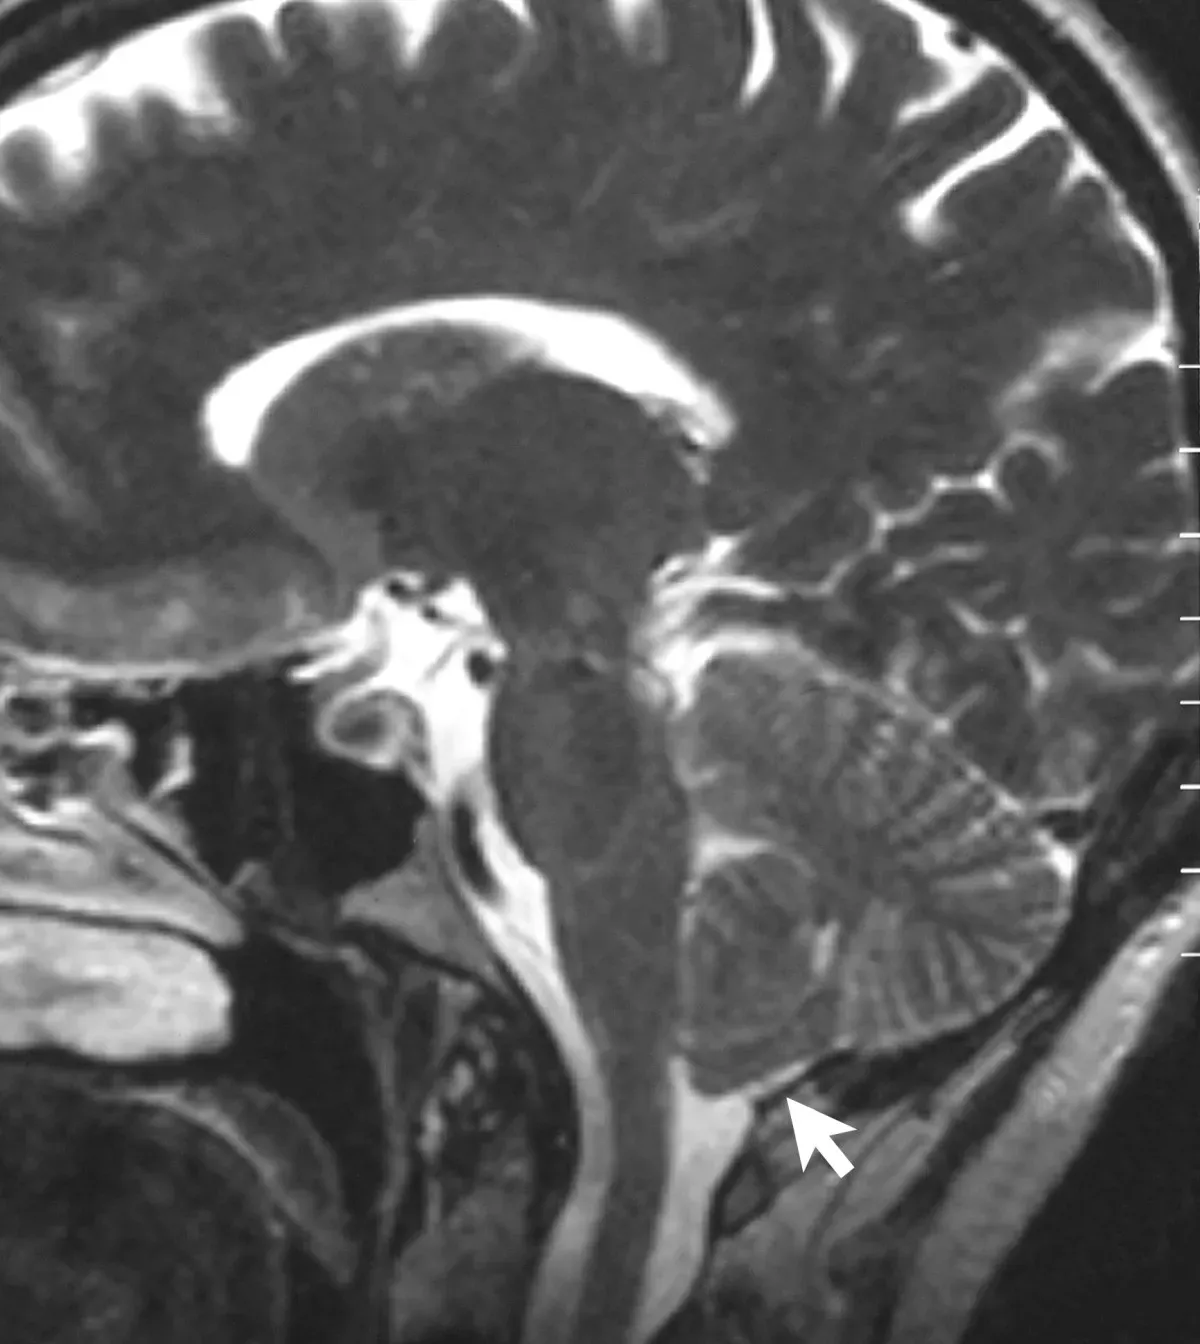

The Hidden Clues in Disorders of Consciousness

Some of the most haunting clues about awareness come from people whose consciousness is altered, dimmed, or trapped. Patients in comas, vegetative states, or minimally conscious conditions push our definitions to their limits. Brain scans have shown that a small subset of patients diagnosed as unresponsive can, when prompted, modulate their brain activity in ways that suggest they understand spoken instructions. In a few famous cases, people who appeared entirely unaware were able to answer yes-or-no questions by imagining specific actions, which lit up corresponding brain regions on a scanner.

These findings raise deeply unsettling questions. If outward behavior can be almost zero while inner awareness persists, how many people might be misdiagnosed, written off, or treated as if they are not there? At the same time, such cases hint that awareness might be more robust than our usual markers – eye tracking, movement, speech – suggest. Yet even when we can say with some confidence that certain brain dynamics support consciousness, we still do not know what turns this set of dynamics into a lived reality. The science is saving lives and reshaping medical ethics, but it has not cracked the underlying riddle.